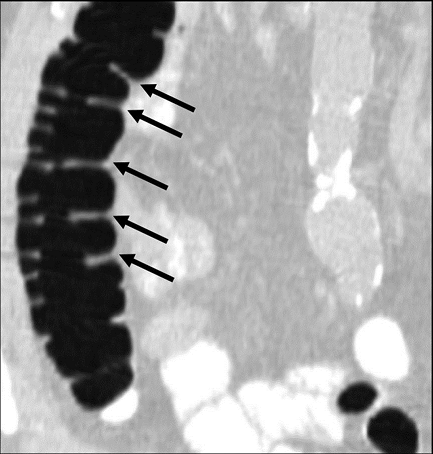

A single reviewer evaluated all data sets using a DICOM image viewer (OsiriX v4.0) for inclusion into this study. Inclusion criteria were: (1) adequate colonic distension and (2) presence of measurable folds. Having a minimum of at least five consecutive measurable haustral fold pairs in a given colonic segment was established as a marker of adequate bowel distention for optimal measurement of folds. Measurable folds were defined as folds that were not obscured or distorted by retained fluid, luminal collapse, tortuosity or diverticulosis. As haustral folds meet at the teniae coli, two of the three folds were each measured with the most dependent fold excluded; the most dependent folds were most often obscured by fluid if present (Figure 1A). Measurements of fold heights were made on 2D multiplanar reformations; the imaging plane demonstrating the folds in cross-section was established for optimal measurement of fold heights (Figure 1B). Due to the high frequency of tortuosity, suboptimal distention relative to other colonic segments, distortion of the folds and diverticulosis relative to other colonic segments, the sigmoid colon was not included in this study.

Figure 1B.Coronal reformat demonstrating adequately distended ascending colon with at least five non-dependent haustral folds (black arrows) clearly visualized. (Multiplanar CT Colonography, Haustral Fold Selection, Axial).

Coronal reformat demonstrating adequately distended ascending colon with at least five non-dependent haustral folds (black arrows) clearly visualized. (Multiplanar CT Colonography, Haustral Fold Selection, Axial).